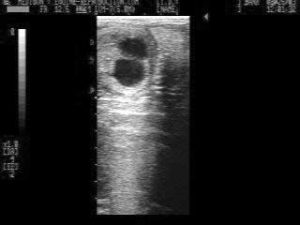

Natural reduction of different sized twin pregnancies seen at days 14, 18 and 33

If the twins are of a different size and touching, one may elect to re-evaluate the pregnancy status no later than day 28 post-ovulation. In the majority of such cases, there is a natural reduction of the pregnancy to a singleton1. For the same reasons listed above, do not hesitate to use prostaglandin at day 28 in the event that you find no apparent reduction, and the presence of two healthy pregnancies!